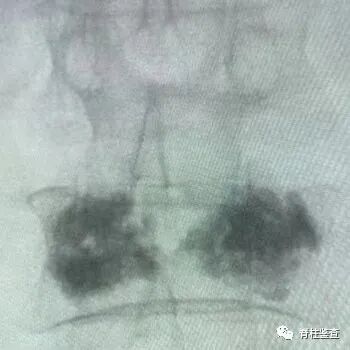

图:PKP和PVP示意图“骨水泥手术”是怎么做的呢?西安市第三医院脊柱外科江伟主任团队通过GIF动图为您介绍如下“骨水泥手术”  Step By Step

• 注射骨水泥

• 椎体恢复高度